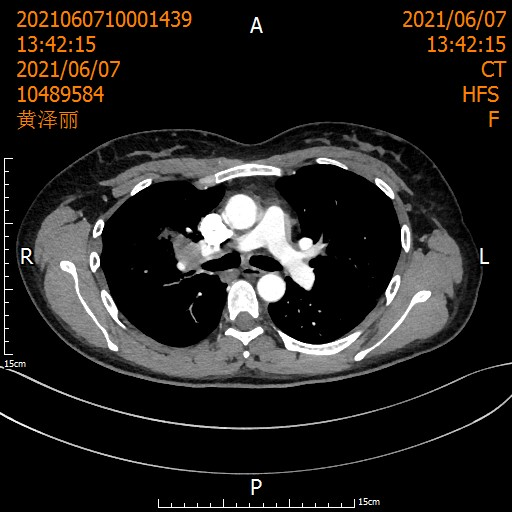

当术后病理报告出炉时,所有人的激动难以言喻: 肺泡上皮增生,间质明显纤维化伴淋巴细胞浸润及淋巴滤泡形成,未见明显肿瘤细胞,切缘阴性,21枚淋巴结0转移——病理完全缓解(pCR)!

从T3到T0,从晚期到根治,这场医患携手创造的奇迹,让整个科室沸腾!

◆ 术后2周期“化免”联合4周期“免疫”巩固治疗——守护来之不易的胜利

◆ 定期门诊复查——像雷达般扫描复发风险